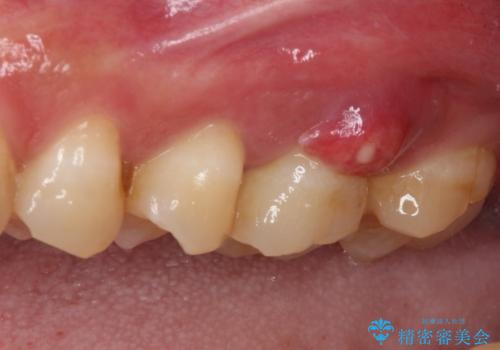

初診時の診察所見では、破折の可能性は低く、根管治療を前提とした治療にて説明をしておりました。

詰められた材料や壊死した組織を除去したところ、鮮明な破折線が認められたため、速やかに抜歯し、傷や骨の治癒を待って、サイナスリフトにより骨高さの低い部分にインプラント埋入を行いました。